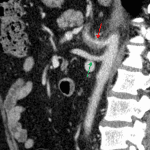

- Circumferential wall thickening of the celiac artery and major branches including the common, proper, and right hepatic arteries and residual splenic artery with surrounding fat stranding

- These inflammatory changes result in up to 50% luminal narrowing without occlusion

- Celiac artery vasculitis

Findings concerning for vasculitis involving the celiac artery and branch vessels, which results in luminal narrowing up to 50%.

Nonspecific edema in the small bowel mesentery, which likely relates to the above findings. No findings to suggest bowel ischemia.